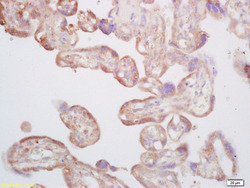

- Main image

- Experimental details

- Formalin-fixed and paraffin embedded human placenta labeled with Rabbit Anti CYP5A1/Thromboxane synthase Polyclonal Antibody, Unconjugated (bs-4019R) at 1:200 followed by conjugation to the secondary antibody and DAB staining

- Sample type

- Human

- Other comments

- Placenta